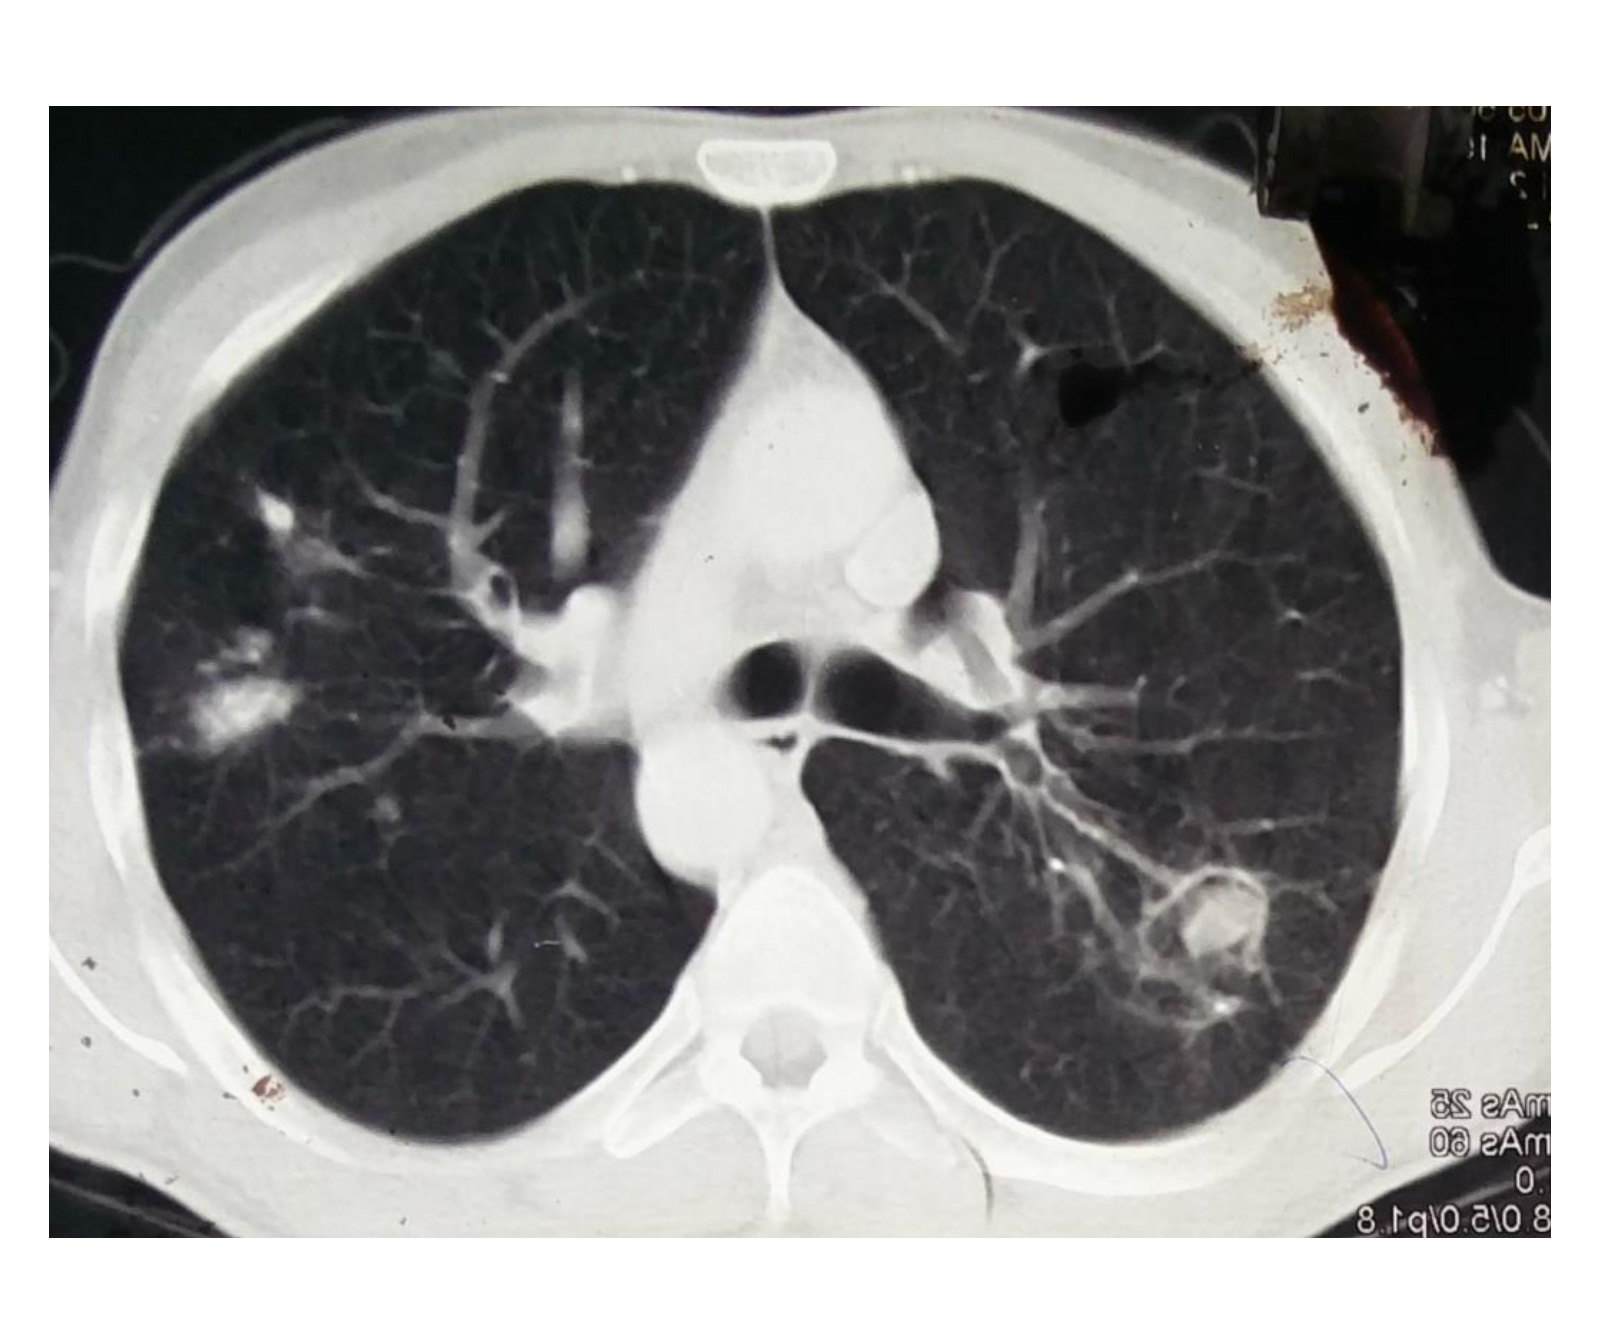

MDR TB is a form of tuberculosis caused by bacteria that are resistant to at least two of the most effective anti-TB drugs. This resistance makes MDR TB more challenging to treat and control compared to drug-susceptible TB.

When TB infection damages the lungs, it can lead to the formation of scar tissue or cavities. These structural changes can weaken blood vessels in the lungs, making them more prone to bleeding. Hemoptysis can occur when these blood vessels rupture, causing blood to be coughed up.

Chest pain can occur as a result of the scarring and fibrosis that develops in the lungs after TB. The pain may be sharp or dull and can be exacerbated by deep breathing or physical activity.

When it comes to Multidrug-Resistant Tuberculosis (MDR-TB), the decision to pursue surgical treatment is typically made on a case-by-case basis. MDR TB is caused by strains of the bacteria that are resistant to at least two of the most powerful anti-TB drugs. It is a serious condition that requires comprehensive treatment.

Surgery may be considered as an adjunct to medical therapy in certain situations. For example, if there is a localised area of infection that is not responding well to medication, surgery may be recommended. Additionally, surgery may be considered for the removal of lung cavities or to address complications such as hemoptysis (coughing up blood).